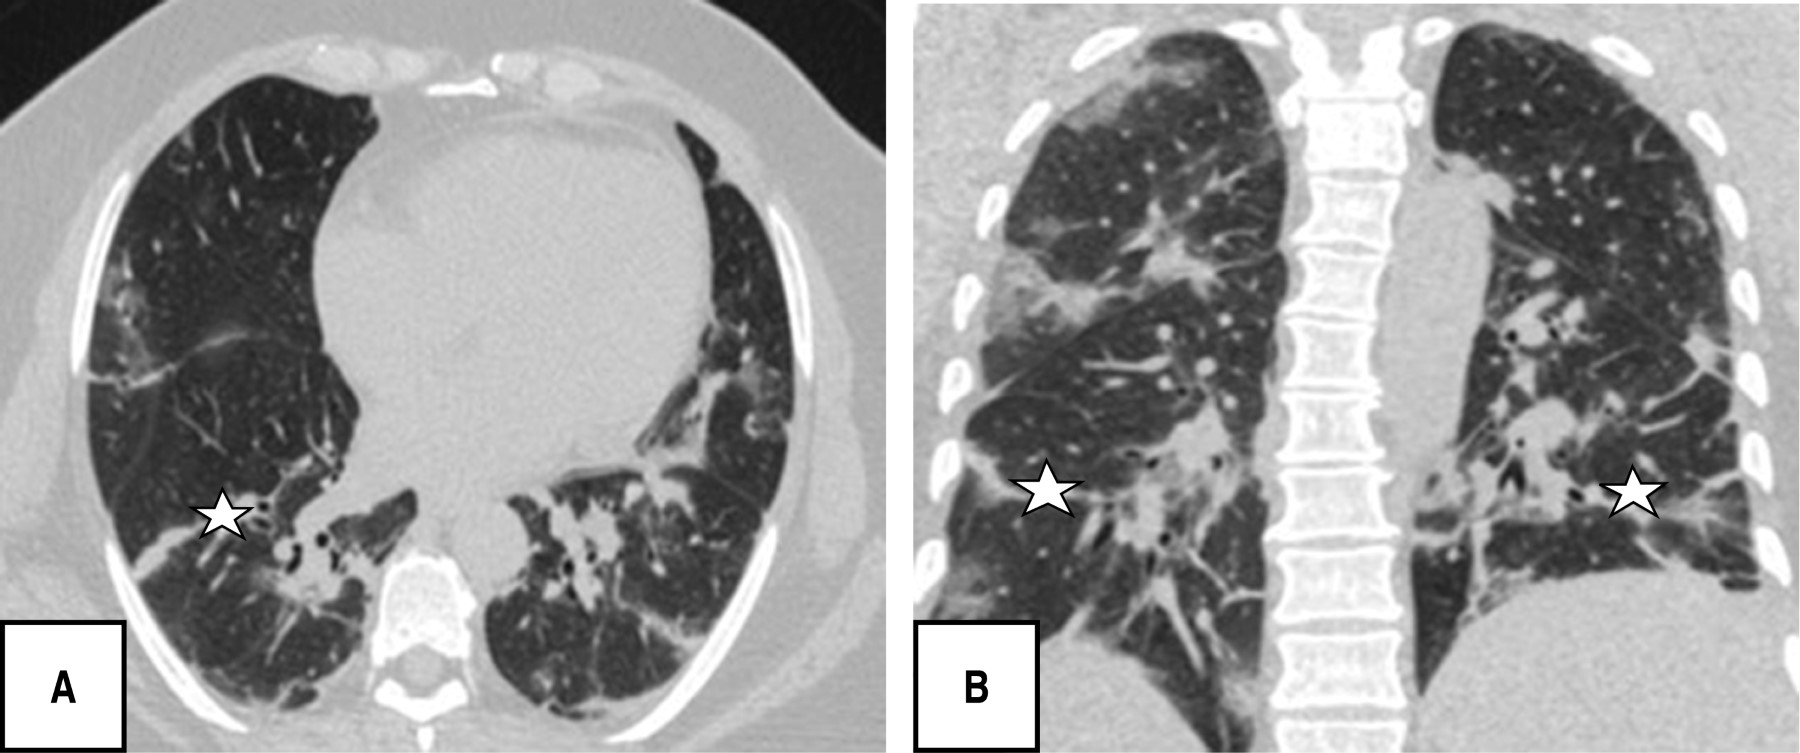

Durante la evaluación tomográfica se obtuvo que los patrones pulmonares más frecuentes fueron: patrón en empedrado (120 [80.5%]), bandas pleuroparenquimales (118 [79.2%]) y patrón en vidrio deslustrado (110 [73.8%]), patrón reticular 82 [55%]), y en menor porcentaje dilatación vascular (56 [37.6%]) y patrón consolidado (52 [34.9%]) (Figuras 1, 2, 3 y 4).

Es de resaltar que la mayoría de los pacientes en esta investigación se presentaron en una fase crónica/avanzada de la enfermedad encontrando como patrones predominantes el empedrado (120/149; 80.5%), bandas pleuroparenquimales (118/149; 79.5%) y en tercer lugar patrón en vidrio deslustrado (110/149; 73.8%), sin identificar ningún caso con hallazgos de atolón, neumotórax o árbol en gemación, otros estudios sí reportan como hallazgo predominante las opacidades en vidrio deslustrado seguido del patrón en consolidación y al respecto el derrame pleural, derrame pericárdico, linfadenopatía, cavitación, el halo reverso o signo del atolón y neumotórax son poco frecuentes, pero pueden observarse con la progresión de la enfermedad.19-21

La afectación de segmentos fue sin predominio y con una distribución central y periférica en igual porcentaje con 57.7%, diferente a lo publicado por Pan F et al., donde los lóbulos inferiores eran más proclives a estar involucrados y en general, la distribución subpleural de las lesiones fue más frecuente que las lesiones pulmonares centrales.22